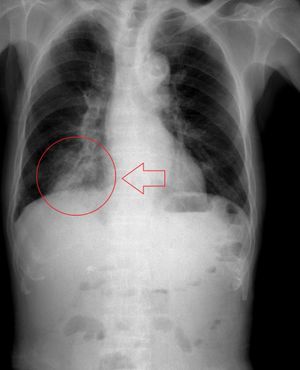

흉부 X-레이는 흡인성 폐렴 진단에 유용할 수 있지만, 초기에는 음성으로 나타날 수 있다.[12] 흉부 CT 스캔 또한 폐렴의 존재를 확인할 수 있으며, 농양, 이물 또는 흉막 질환의 특성 파악에도 도움이 될 수 있다.

투시경 검사 연하 검사는 연하곤란 또는 운동 장애가 흡인의 원인으로 생각되는 경우에 수행할 수 있다. 음식과 음료를 바륨 조영제와 혼합하여 X-레이를 사용하여 연하를 평가한다. 조영제가 성대 아래로 기관으로 흘러 들어가는 경우 흡인으로 진단할 수 있다.[13]